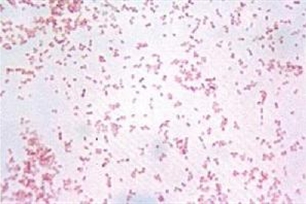

一种微生物。属卵圆形或杆状革兰氏阴性、发酵性的微小杆菌。寄生在哺乳类及鸟类中,无固定寄生部位,肺与血液等均会发现,可引起败血症或呼吸道感染等病症。由法国细菌学家巴斯德(Pasteur) 发现。

【巴氏杆菌】 图片鉴赏